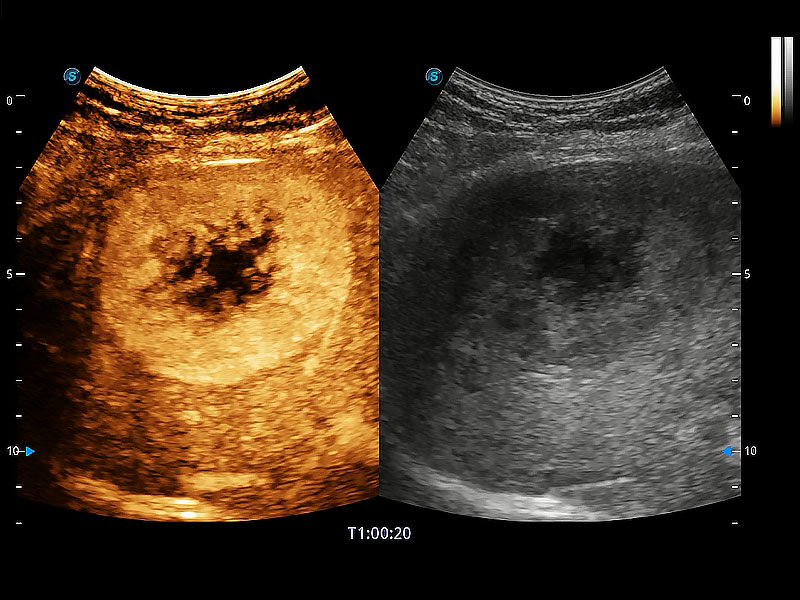

(犬)肝脏

(猫)胆囊

(犬)胎儿主动脉弓立体血流

(犬)肾脏显微血流

(犬)胎儿四腔心